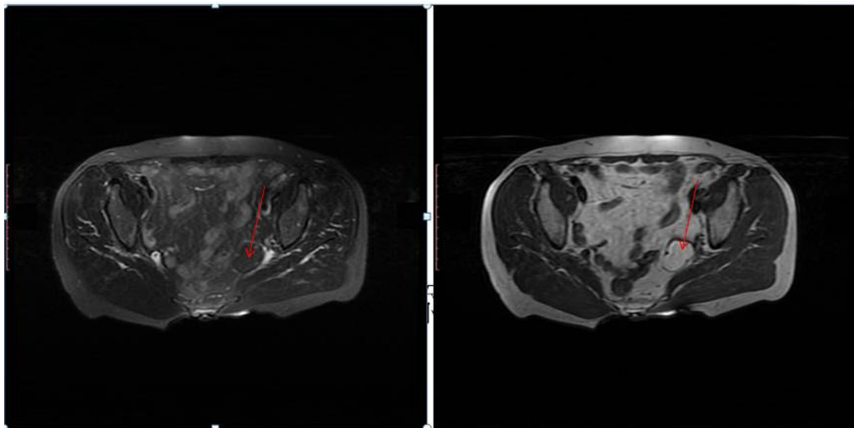

【诊断过程】影像学检查显示左附件区24 mm×38 mm×51 mm混杂密度肿块,CT见脂肪样密度区,MRI呈现短T1/T2信号与等信号交替,经阴道超声测得28 mm×19 mm实性肿块伴不规则无回声区